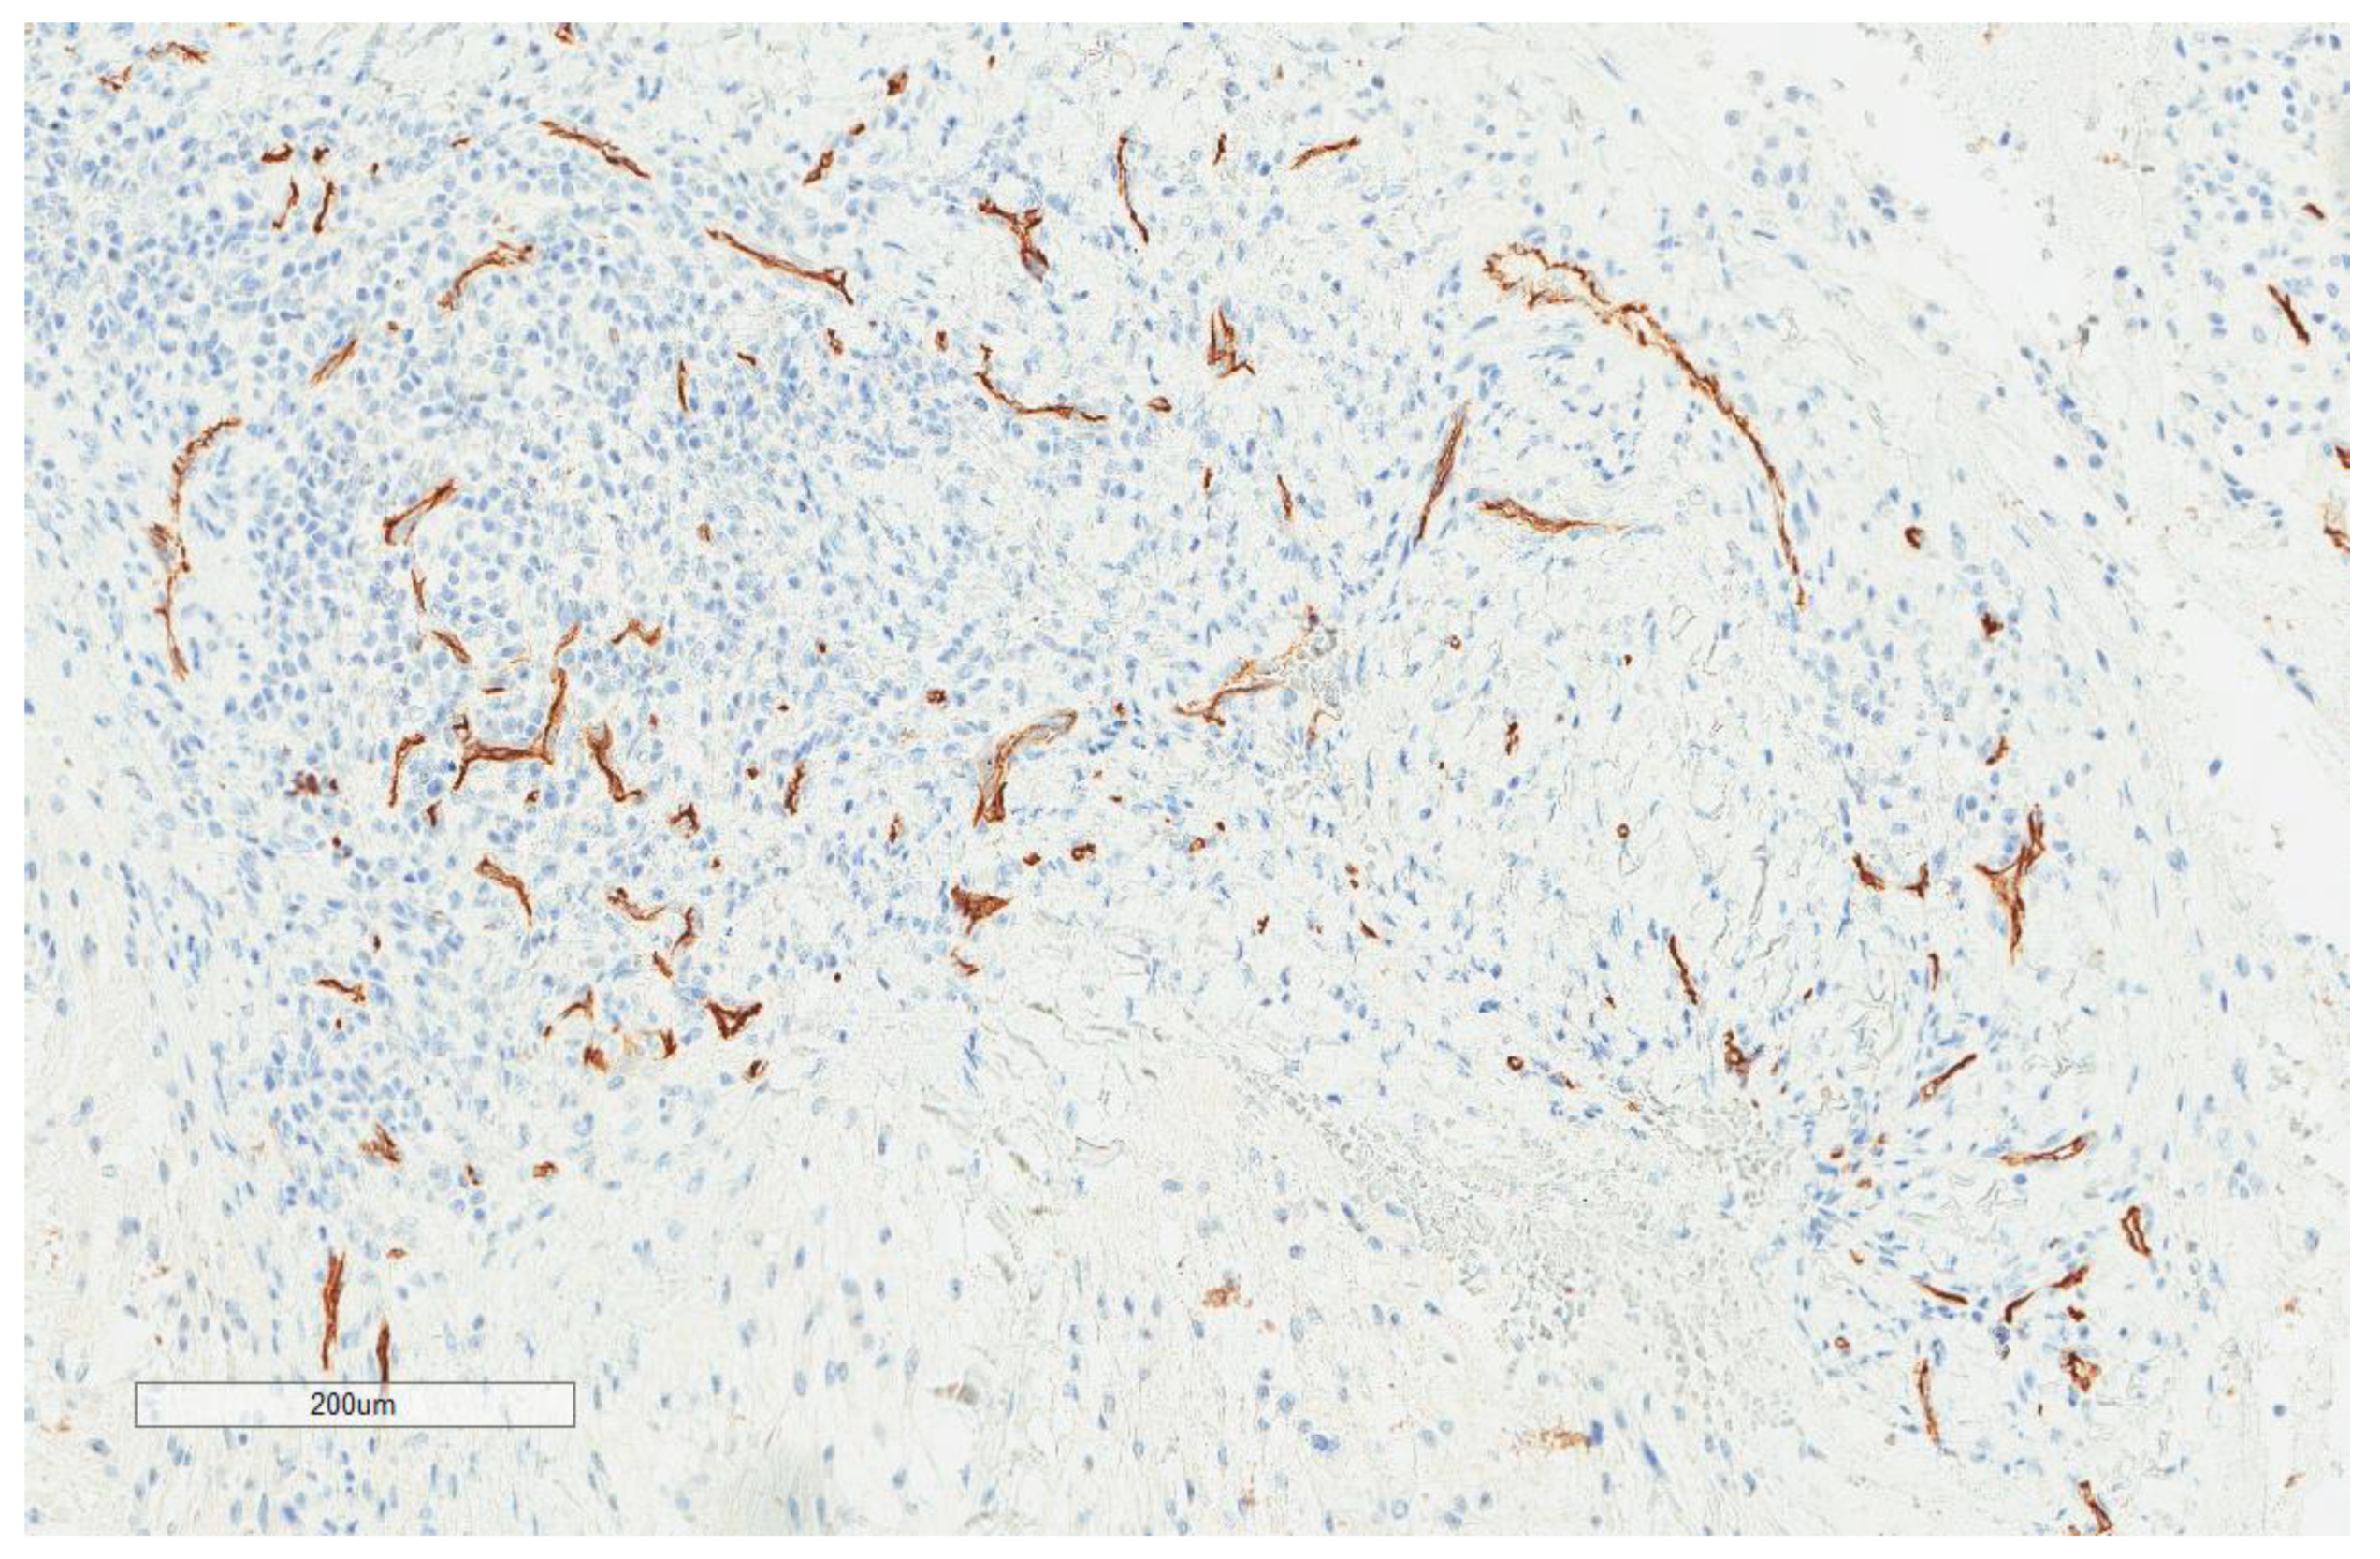

| CD34 vascular density (n = 74) | |

| Range | 1–22 |

| Median (High and Low, n,%) | 3.5 (37, 50% and 37, 50%) |

| Mean ± SD | 5.8 ± 5.7 |